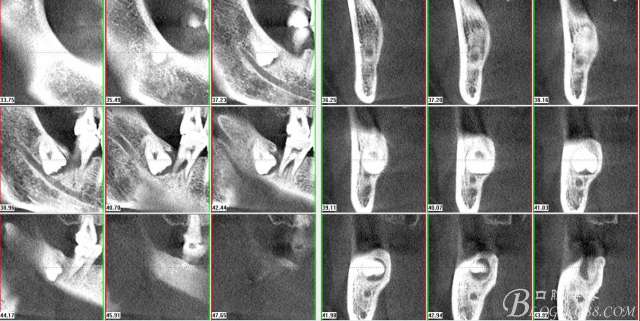

圖3.通過(guò)矢狀面和冠狀面來(lái)判斷48與下頜管及47的關(guān)系

圖4.水平方向48與47之間的關(guān)系

圖6.測(cè)量48頰、舌側(cè)骨板厚度。

圖7.測(cè)量牙冠近遠(yuǎn)中徑的大小及遠(yuǎn)中骨板的厚度